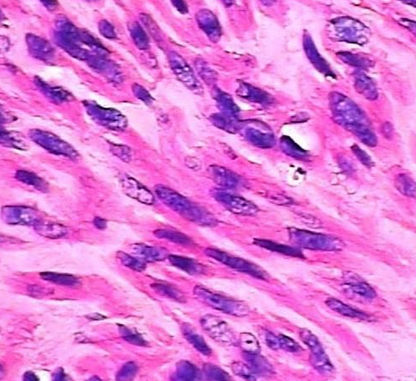

6.病理检测:HE染色、特殊染色、组织切片、免疫组化、流式细胞分选

做肿瘤研究的人,很少有不知道 transwell 实验的,它是用来研究肿瘤细胞的迁移侵袭转移情况的一种简便快捷的实验方法,还可以构建两种细胞的共培养体系以及趋化性试验。今天咱们就来讲讲怎么做肿瘤细胞的侵袭转移实验。Transwell 侵袭实验,其实原理简单地说就是用一层膜将高营养的培养液和低营养的培养液隔开,细胞放在低营养的培养液里,为了找吃的,细胞会往高营养的培养液里面跑,但是有膜挡着,所以要穿过膜才行。我们在膜上涂上一层基质胶,模仿细胞外基质,于是细胞就要分泌金属蛋白酶将基质消化